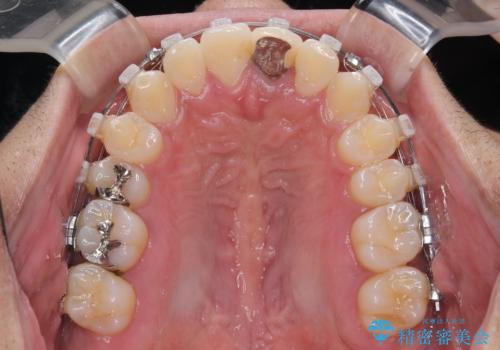

- 前歯のデコボコや八重歯を気にして来院された患者様です。

他院でワイヤー矯正を行うつもりでいらっしゃったそうですが、通院が難しくなったとのことで当院での治療を希望されて来院されました。

上下ともに歯列幅が狭く、その影響でデコボコになっていたため、ワイヤー装置を用いて歯列を側方に拡大しながら、デコボコを解消していくこととしました。